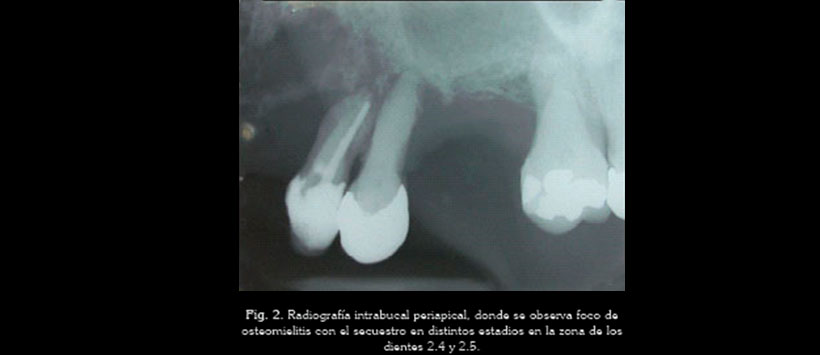

El análisis radiográfico revela una zona radiolúcida extensa de densidad alterada con presencia de secuestros óseos en la región de los dientes 2.4 y 2.5 (Figura 2). Fue prescrito Amoxicilina (500 mg, vía oral) 1 cápsula cada 8 horas durante 14 días y cirugía con cita para después de 7 días de haber empezado el tratamiento con el antibiótico.